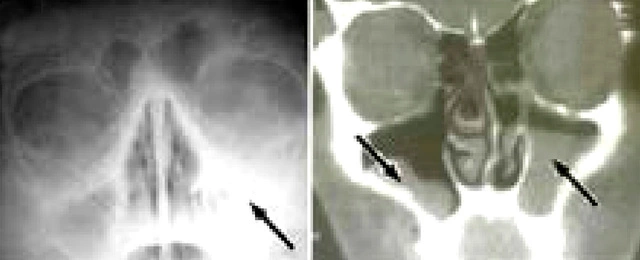

Кроме того, врач может направить пациента на пункцию, если рентгеновские снимки показывают воспаленные участки, которые не поддаются медикаментозному лечению.

Направить на пункцию может врач, если медикаментозное лечение не дало нужных результатов.